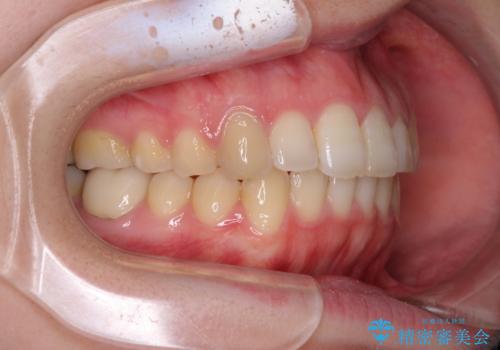

- 口の閉じにくさと割れてしまった奥歯を気にして来院された患者様です。

IPR(歯と歯の間を削る)と歯列全体の後方移動によって口元が引っ込むように設計し、インビザラインにより治療を行うこととしました。

上下正中がずれていたため、抜歯による矯正治療も検討しましたが、口元がそれほど突出していなかったため、非抜歯にて矯正することになりました。

その結果正中のズレは残りましたが、口を閉じたときの感覚や奥歯の咬み合わせには全く問題なく、患者様には大変満足していただきました。